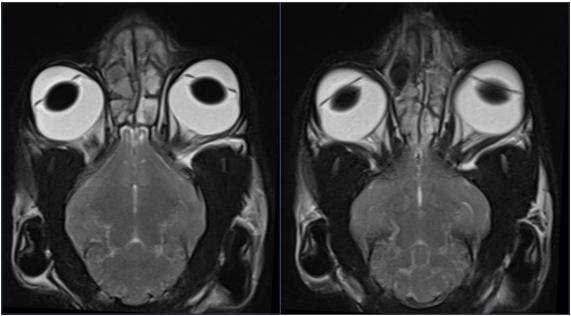

核磁↓↓

核磁结果显示:双侧鼻腔、额窦及额前部皮下可见T1WI等信号、T2WI高信号内容物;双侧局灶

性鼻甲纹理缺失,右侧鼻腔较明显,且右侧鼻骨局灶性溶解;左侧额骨增厚,额窦腔隙较小;腹侧筛板影像不清,双侧嗅球部脑膜T2WI信号增强。小脑尾侧部分实质突入枕骨大孔。双侧鼓室呈T1WI、T2WI低信号,鼓泡壁平滑。

猫咪常年耳朵流脓,经过在其他医院核磁检查在我院进行了垂直耳道切除术,希望早日康复吧↓↓